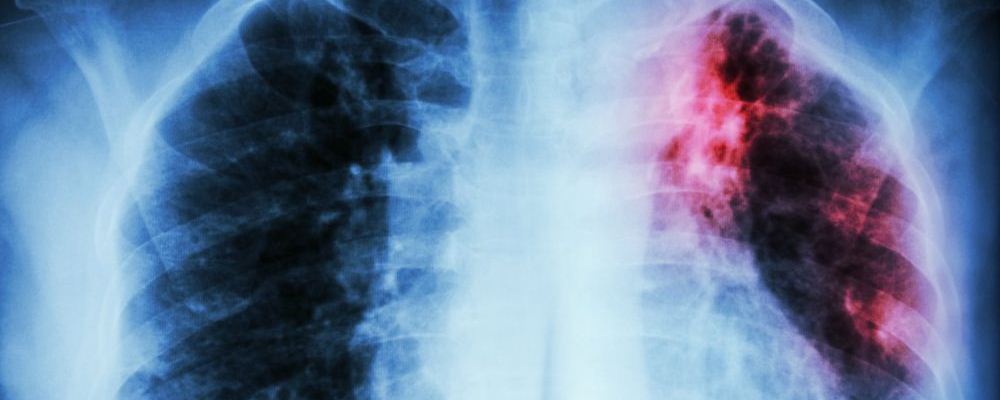

肺癌可是很可怕的疾病,其發(fā)病率和死亡率都很高,是一種威脅人的健康和生命的惡性腫瘤。早期發(fā)現(xiàn)問題治療恢復(fù)的可能性比較大,可是到了肺癌晚期的時候,就算就回來了也沒幾年好活了。可是,最近湖南有個家庭發(fā)生了一件糟心的事情——12男孩患上原發(fā)性支氣管肺癌晚期疾病。這實在是令人震驚,這么小的年紀(jì)就得了這種病。

近日,湖南邵陽一名12歲男孩因鎖骨處長包塊,到醫(yī)院檢查,竟然得了原發(fā)性支氣管肺癌晚期!這種癌癥患病率和死亡率位居全球第一,但在未成年人中比較罕見。而造成此種疾病的原因,竟然是“懶,經(jīng)常熬夜,早餐基本上不吃!”